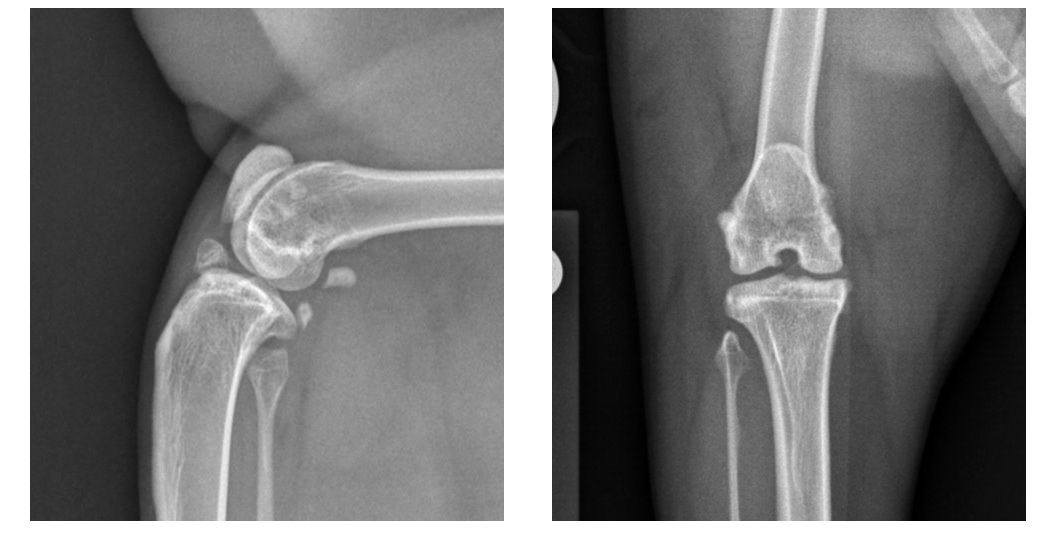

Both of Sophie’s stifles (knees) suffered from medial patellar luxation – or, when a kneecap dislocates or moves out of its normal location toward the inside of the limb. She also suffered rupture of the cranial cruciate ligament (the feline equivalent of the anterior cruciate ligament, or ACL, in people) on the right.

Perry’s team conducted an orthopedic examination and collected X-rays to properly diagnose Sophie. They found that her right patella would intermittently luxate, or dislocate, toward the inside of the limb. Additionally, there was instability in the right stifle, with the tibia (shin bone) being able to move forward relative to the femur (thigh bone) when the limb was weight-bearing. This instability indicated that her cranial cruciate ligament was ruptured. Patellar luxation also was evident affecting her left stifle, but her cranial cruciate ligament was intact on that side.

Sophie’s final diagnosis was bilateral medial patellar luxation and concomitant right cranial cruciate ligament rupture – similar to a dislocated kneecap and torn ACL in a human, Perry explained. “